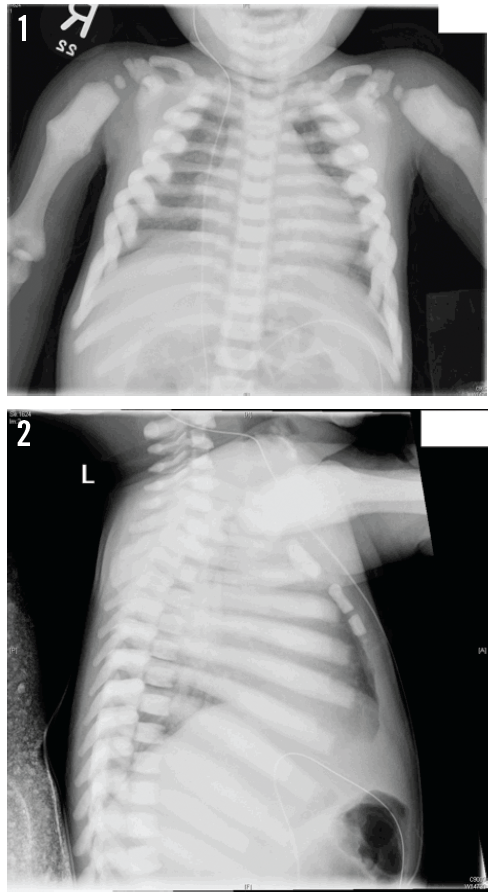

Radiographs were ordered. On the anteroposterior view (Figure 1), the visualized osseous structures demonstrated diffuse, chalky, increased density. The callus deformities of both proximal humeral shafts may be suggestive of old fractures. On the lateral view (Figure 2), the vertebral bodies demonstrated a “sandwich” appearance, with increased endplate sclerosis.

Answer: Osteopetrosis

Based on these findings, the child received a preliminary diagnosis of osteopetrosis, a hereditary disorder in which pathologic alteration of osteoclast resorption results in the thickening of cortical and lamellar bone.1 The diagnosis was confirmed with genetic testing, the results of which revealed an autosomal recessive, homozygous mutation of the T-cell immune regulator 1 gene, TCIRG1.